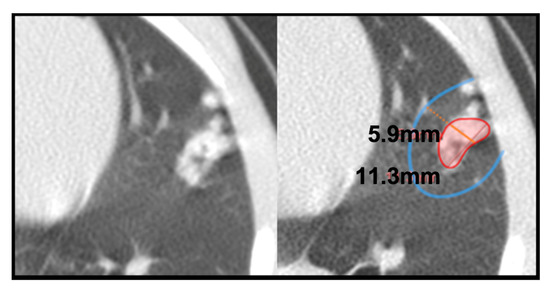

2.4. TB Lung Lesions Analysis from CT Images

- A.

- Micronodule is a small solid lung nodule with smooth margins.

- B.

- Consolidation (also referred to as consolidated lesion) is a pneumonic patch or necrotizing consolidative process that occupies and even destroys alveoli, and it is described in CT images as a soft tissue lesion within lung parenchyma showing irregular margins.

- C.

- D.

- Pleural distance is defined as the distance between the margin of each consolidation to the closest pleura or fissure.